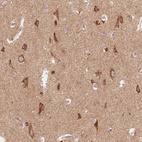

Immunohistochemical staining of human cerebral cortex shows moderate positivity in neuronal cells.